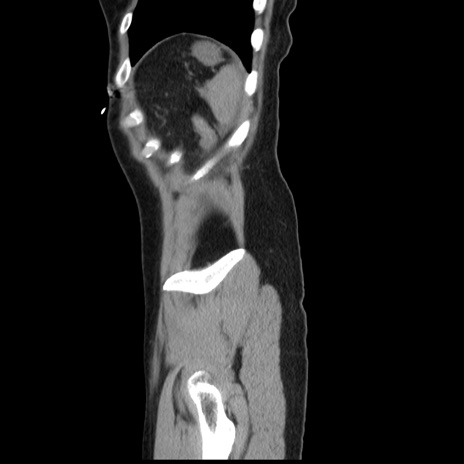

症例10(矢状断像)

【症例】 50歳代女性

【主訴】 腹痛

【現病歴】前日生レバーを食べた。今朝に排便あり。 昼前に突然発症の腹痛を生じ、当院救急外来を受診した。

【既往歴】 子宮筋腫にてで子宮全摘後

【身体所見】 意識清明、腹部:平坦、軟、下腹部やや左を中心に圧痛・反跳痛あり、筋性防御あり

【データ】WBC 7800、CRP 0.07